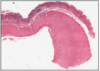

EPIGLOTTIS

- @ posterior of tongue

- boundary of oropharynx and laryngeal pharynx

- mostly SSNKE

- lower part posterior - pseudo-stratified columnar ciliated epithelium (respiratory)

contains:

- elastic cartilage plate

- lymph nodules (submucosa)

- salivary glands (submucosa)

Box A = buccal surface - faces mouth

EPIGLOTTIS 2

- SSNKE